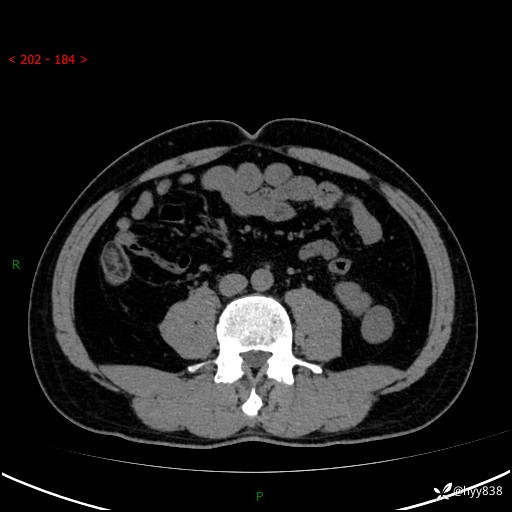

中年男性,左侧腰背部间断性胀痛不适。第一眼“乳头或囊肿”,有无意外---(有结果)

【患者信息】:41岁/男

【主诉】:左侧腰背部间断性胀痛不适1周

【现病史及既往史】:患者1周前无明显诱因出现左侧腰部疼痛,呈间断性胀痛,休息后可缓解,无放射痛,偶可见肉眼血尿,无血块,无尿频尿急尿痛,无夜尿增多,无畏寒发热、咳嗽咳痰等症状。于我院查双肾CT示:左肾占位性病变,左肾下极囊性病变,左肾轻度积水,胆囊多发结石。今为求进一步诊治来我院,门诊以“左肾占位性病变”收治入院。 起病以来,患者精神佳,饮食、睡眠良好,大便正常,小便如上诉,体力体重无明显变化。

【检查】:肾脏CT平扫+增强